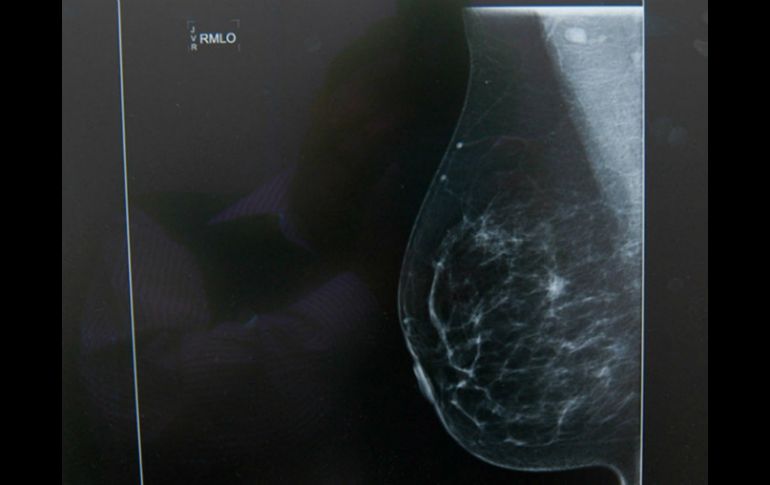

Tecnología | La Elf5 favorece durante la producción de leche y después deja entrar células cancerosa Una proteína, clave en la lactancia y cáncer de mama La Elf5 favorece durante la producción de leche y después deja entrar células cancerosas Por: EFE 30 de diciembre de 2015 - 17:10 hs La proteína adquiere un papel pro-tumoral produciendo metástasis lo que favorece a la enfermedad. NTX / ARCHIVO MADRID, ESPAÑA (30/DIC/2015).- Un equipo de investigadores ha constatado que una proteína que controla la producción de leche durante la lactancia materna se "descontrola" en el cáncer de mama, lo que favorece la entrada de las células cancerosas en el torrente sanguíneo y su diseminación por el organismo (metástasis). Esta "doble cara" de la proteína Elf5 se publica en la revista científica Plos Biology, en un artículo que lidera el español David Gallego-Ortega, ahora en el Instituto Garvan de Investigación Médica de Sídney (Australia), junto al profesor Christopher Ormandy. Elf5 es una proteína imprescindible para la lactancia materna, una función que ya fue descrita por Ormandy en 2008: en condiciones normales, durante el período de gestación, Elf5 entra en funcionamiento preparando a las células de mama para la producción de leche durante la lactancia, explica a Efe Gallego-Ortega. Sin embargo, y esto es lo que se describe en este trabajo, en células de cáncer de mama esta proteína adquiere un papel pro-tumoral produciendo metástasis, señala este investigador. "Hemos encontrado altos niveles de Elf5 en pacientes de cáncer de mama de tipo lunimal A (la forma más común) que presentan una enfermedad avanzada y demostramos cómo Elf5 es capaz de producir la diseminación del cáncer de mama al pulmón en modelos animales", afirma Gallego-Ortega en una nota del instituto australiano. Este investigador detalla que el gran problema en cáncer de mama es la aparición de lesiones secundarias -metástasis-, que son las que acaban con la vida del paciente. "La 'cara negativa' de Elf5 es que células que la expresan son capaces de engañar al sistema inmune para que se produzca inflamación en el tumor y como consecuencia a esta inflamación se incrementa la aparición de metástasis", apunta este científico vía correo electrónico. El tipo luminal A es la forma más común de cáncer de mama y es por tanto el que produce más muertes. Este estudio se ha centrado en este subtipo porque los investigadores tienen un trabajo previo publicado en 2012 -también en Plos Biology- en el que se relacionaba Elf5 con la resistencia a terapias en este subtipo en particular, así que decidieron profundizar en este tipo concreto y extender la investigación. "En un estudio anterior demostramos que Elf5 está implicado en el desarrollo de resistencia a terapias y con los datos de este nuevo descubrimiento vemos cómo Elf5 está implicado en dos de los aspectos más agresivos del cáncer de mama: resistencia a fármacos y metástasis". En este sentido, este científico subraya que en los ratones empleados para este estudio pudieron ver inmediatamente una fuerte inflamación y la aparición de un mayor número de metástasis en pulmón cuando los niveles de Elf5 estaban altamente elevados. Para este investigador, la constatación de que una proteína tiene doble función "antagónica" es un proceso frecuente en biología: todo depende del contexto, para "simplificar a mí me gusta decir que el cáncer secuestra y maligniza las funciones normales de las proteínas para su propio beneficio". Gallego-Ortega relata que este trabajo abre una nueva puerta para el tratamiento del cáncer de mama usando fármacos dirigidos contra las células inflamatorias. Una característica clave es que estos fármacos podrían ser usados en combinación con las terapias actuales. "Elf5 jugaría un papel de biomarcador para identificar qué pacientes se beneficiarían de esta terapia, en función de la presencia o ausencia de Elf5". Temas Investigación científica Ciencia médica Células Cáncer de mama Leche materna Lee También INAPAM: ¿Cómo solicitar un turno para consulta médica gratuita? Investigación de Rancho Izaguirre no está archivada; 12 funcionarios están involucrados Octubre Rosa: ¿Cuánto cuesta una mastografía en Jalisco según Profeco? Nobel de Química premia el desarrollo de estructuras metal-orgánicas Recibe las últimas noticias en tu e-mail Todo lo que necesitas saber para comenzar tu día Registrarse implica aceptar los Términos y Condiciones